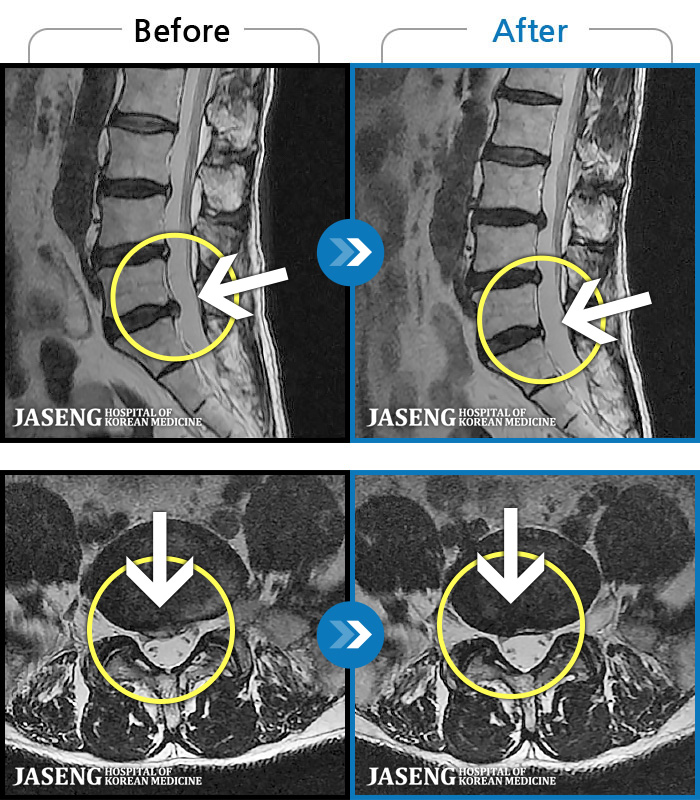

[] 03.04.01~09.11.01